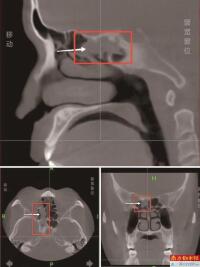

• 鼻窦炎反复发作18年 元凶竟是3cm树枝

以为只是普通的鼻炎、鼻窦炎,辗转求医18年,保守治疗效果不佳。谁曾想,困扰他多年的“真凶”,竟是一截深藏在鼻窦深处、长达3厘米的树枝!近日,深圳大学总医院耳鼻喉科精准“破案”,为阿杰(化名)解除了